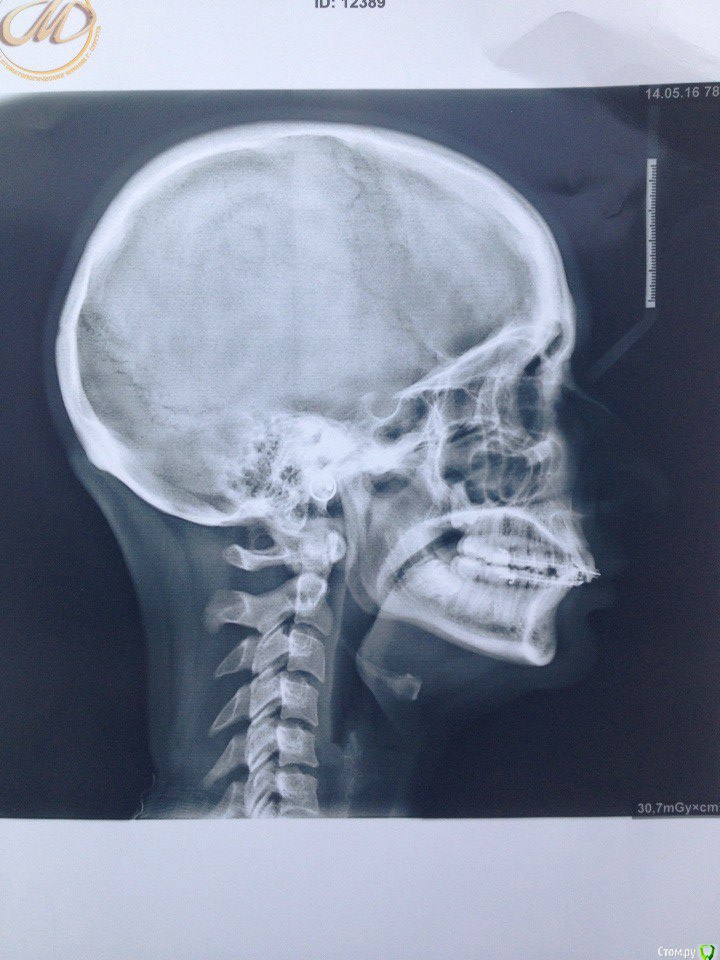

Поставила керамические брекеты в марте 2015 года, ставила для выравнивания зубов (торчали два передних зуба на нижней и на верхней челюсти), проблем с ВНЧС не было, только скрипела во сне зубами, муж неоднократно замечал. На первичной консультации отртодонта предупредила о бруксизме, сказал все нормально, все подобные проблемы именно брекетами и лечатся. Перед установкой делали только ОПТГ и фотографии. Прикус был немного глубокий, как я сама понимаю, во всяком случае от врачей никогда не слышала, что у меня какой-то неправильный прикус. Через месяц после ношения брекетов перестал открываться рот, просто к вечеру я заметила, что не могу его открыть широко, не влазила даже ложка, на осмотре у ортодонта он немножко подпилил накладки, которые были установлены на 6 зубах на НЧ. Ничего не изменилось, на след.осмотре убрал накладки совсем, рот начал открываться, через щелчок или хруст, но не прямо, для широко открытого рта мне приходится делать движение вправо и только так рот открывается до конца, сильных болей не было и нет, бывает ноет в левой стороне возле уха. через несколько месяцев ношения брекетов начала замечать, что челюсть уходит вправо. Вообще на протяжении всего ношения брекетов испытывала дискомфорт в мышцах, все тянуло, и какие то тяжелые челюсти казались. 15 мая сняли брекеты, сделали слепки для капп, мой ортодонт сказал, что сейчас нужно удалять все оставшиеся 8 и походить к остеопату или мануальщику, если не поможет возвращаться делать аксиографию и ставить другие брекеты, на вопрос чем они отличаются он ответил, что с ними можно зуб наклонять в любом положении, в отличии от этих, т.к. с этими брекетами зубы встают только на 90градусов, после снятия брекетов чувствую себя хуже, боль начала появляться в левом ухе, ужасно все напряжено. В нашем городе гнатологов и подобных специалистов нет, ходила на протяжении года к нескольким ортодонтам на консультацию никакой конкретики, грубо говоря все пожимали плечами, не знаю как быть, какие обследования пройти, не поторопились ли мы снимать брекеты (он настаивал), и к кому обратиться, ваше мнение с чем это связано и как теперь решить проблему?